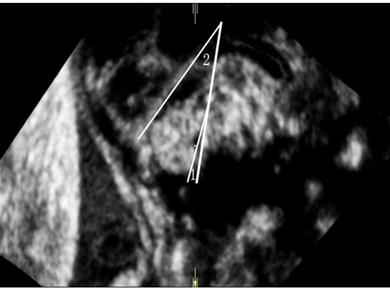

注:角1为BV角,角2为BT角 图3 胎儿头颅正中矢状切面显示正常胎儿BV角、BT角的测量

注:1为BV角,2为BT角

图4 正常胎儿BV角、BT角的测量,显示测值分别为2.4°、25.0°